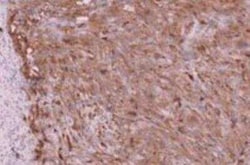

CA19-9/Sialyl Lewis A Monoclonal antibody specifically detects CA19-9/Sialyl Lewis A in Human samples. It is validated for Flow Cytometry, Immunohistochemistry, Immunofluorescence, Immunohistochemistry (Paraffin), Immunofluorescence

| Flow Cytometry 0.5 - 1 ug/million cells in 0.1 ml, Immunohistochemistry, Immunocytochemistry/Immunofluorescence 1-2 ug/ml, Immunohistochemistry-Paraffin 0.5 - 1.0 ug/ml, Immunofluorescence 0.5 - 1.0 ug/ml | |

| Flow Cytometry, Immunohistochemistry, Immunofluorescence, Immunohistochemistry (Paraffin), Immunofluorescence | |